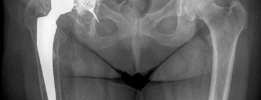

Based on the preoperative plain radiographs and advanced CT imaging, this patient's defect was classified as a severe Paprosky Type IIIA defect.

* Superior Migration: The component had migrated superiorly greater than 3 cm, indicating severe loss of the superior dome and structural support.

* Medial Migration: The component had breached Kohler's line, indicating a deficient medial wall and protrusio.

* Ischial Osteolysis: Moderate osteolysis was present extending into the ischium.

* Teardrop Integrity: The teardrop was attenuated but remained partially intact, differentiating this from a Type IIIB defect (where the teardrop is completely obliterated, and severe ischial lysis is present).

* Pelvic Discontinuity: The CT scan confirmed intact anterior and posterior columns, ruling out a Paprosky Type IV defect.